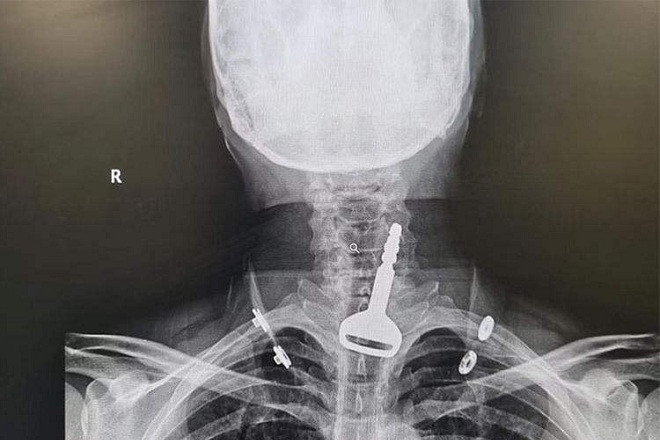

Bác sĩ Lin cho hay, nếu bệnh nhân nuốt phải các vật sắc nhọn, nam châm, xương cá, hoặc xương gà thì có nguy cơ thủng thực quản rất cao. Nếu dị vật nằm dưới thực quản, bác sĩ cần lấy dị vật ra bằng ống nội soi. Trước khi nội soi, bác sĩ cần chụp X-quang để xác định vị trí dị vật.